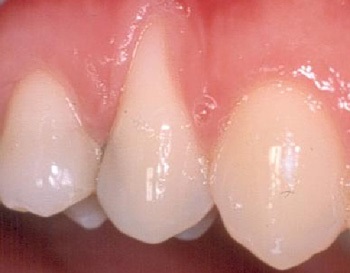

Υποχώρηση ούλου από τραυματικό βούρτσισμα

Υποχώρηση ούλου που οφείλεται σε τραυματικό βούρτσισμα